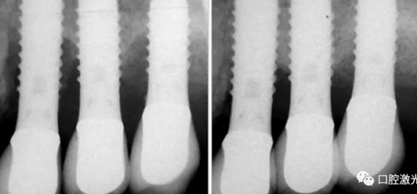

激光輔助種周炎手術(shù)治療前,中和手術(shù)后4年